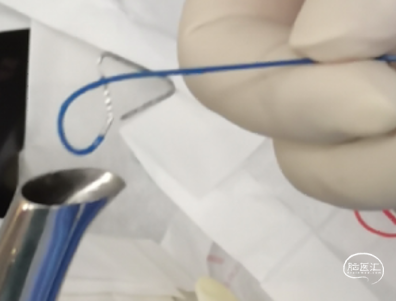

微导管3D评估动脉瘤与载瘤动脉关系

解决WEB输送时血管移位和动脉瘤形态改变导致WEB释放和打开贴壁困难的措施:1、VIA27微导管塑形;2、心玮5F125中间导管内置入:VIA27+snychro0.14 3米导丝,预置导丝作用:1)、提供支撑,避免web推挤过程支撑不足;2)、保护A3动脉,必要时球囊扩张;3)、web按摩。

WEB选择:理想SL9x3(没有),选择SL8x4

直接测量:7.4x3.92mm

3D测量:7.22x5.35mm

对比测量:8.9x4.8mm(偏大10%)

微导丝支撑和保护下WEB释放